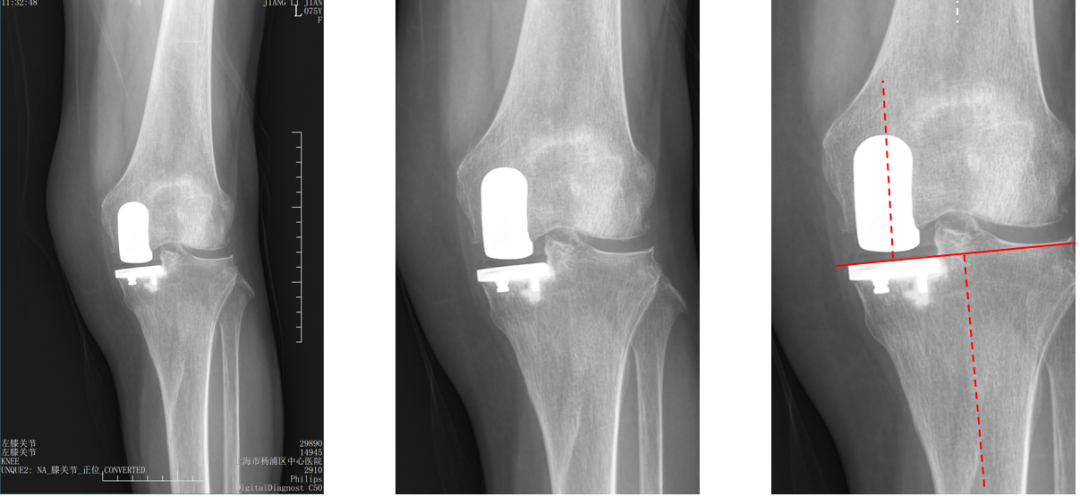

标准胫骨假体位置

AP位胫骨与股骨假体位置:水平截骨与胫骨轴线垂直,无明显内外翻,内侧缘与胫骨平台内侧缘齐平; 股骨假体中线与胫骨假体中线一致。

标准胫骨假体位置(KA)

AP位胫骨与股骨假体位置:水平截骨与胫骨轴线 3°内翻截骨,内侧缘与胫骨平台内侧缘齐平; 股骨假体中轴线与胫骨假体垂直,股骨假体中线与胫骨假体中线一致。

标准股骨假体位置

侧位胫骨与股骨假体位置:胫骨假体后倾7°,前后缘齐平;股骨远端截骨面与股骨长轴垂直,股骨后髁假体后倾15°,完整包容股骨后髁。

胫骨假体厚度合适

胫骨垫片厚度合适:术前内翻畸形基本矫正,残留2-3°内翻。